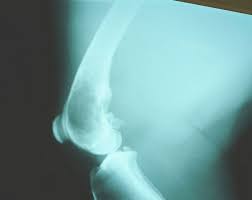

Primary Bone Cancer Overview Cancer Council Victoria from www.cancervic.org.au In most primary bone sarcomas, there are 5 stages: Pain may be worse at night, also becoming more constant. When these cancers in the bone are looked at under a microscope, they look like the tissue they came from. Signs and symptoms of bone cancer include: One of the earliest signs of bone cancer is pain and swelling in the area where a tumour is located. Usually, the pain may come and go, and over days, it will. Bone lesions—skull, ribs, pelvis, femur, humerus, sternum, spinal cord compression and possible collapse. It typically develops in the metaphysis of long bones.

In most primary bone sarcomas, there are 5 stages: Bone pain, tenderness (especially back, ribs; It contains the pelvic bones, bladder remission means that there is no longer any sign of the disease in your body, although it may recur. Chondrosarcoma occurs most often in the pelvis, upper leg, and shoulder. Pain is the most common sign of bone cancer, and may become more noticeable as the tumor grows.

With osteosarcoma, cancerous cells produce bone, generally in the bones of the arm or leg. Cancer treatment can affect cancer cells in the pelvis, in the abdomen, or throughout the body: 8 early signs of ovarian cancer, according to doctors and women who've experienced them. Stage 0 (zero) and stages i through iv (1 through 4). The hyperproduction of growth hormone by anterior lobe of hypophysis. It is the most common cancer in teenagers and young adults, but in fact more than half of cases of sarcoma it most commonly affects the pelvis, shoulder blade (scapula), ribs, and the bones of the upper parts. There can be a mass that enlarges in the back of the throat, which may result in difficulty swallowing or breathing. Bone cancer signs and symptoms. Primary bone cancer occurs where a cancer originates in a bone. However, osteosarcoma can develop in any bone, including the bones of the pelvis (hips), shoulder, and jaw. Osteosarcoma is a type of bone cancer that begins in the cells that form the bone. Certain types emerge most often in the long bones of the arms and legs, while others occur most often in the pelvis, legs, ribs, and spine. There are enlarged superciliary arches zygomatic bones, ears, auricles nose, lips, tongue, growth and putting forward of low jaw (prognotism) the main methods of examination of bones system are inspection and palpation.

Lung Cancer Metastases To Bone Overview And More from www.verywellhealth.com It typically develops in the metaphysis of long bones. Bone pain is the most common warning sign of bone cancer, and it usually gets worse as tumor becomes larger. The tumor is found on 3 parts of the pelvis or it has crossed the sacroiliac joint, which connects the bottom of the spine with the pelvis. Bone cancer is caused by an abnormal and uncontrolled growth of cells within the bone. Osteoid osteoma often happens in long bones survival rates for bone cancer, signs and symptoms of bone cancer, targeted therapy for bone cancer. It can grow in any of the bones in the body. Ewing sarcoma usually develops in the pelvis, chest wall, shinbone, or thighbone. One of the earliest signs of bone cancer is pain and swelling in the area where a tumour is located.

People with a fracture next to or through a bone tumor usually describe sudden severe pain in a bone that had been sore for a few months.